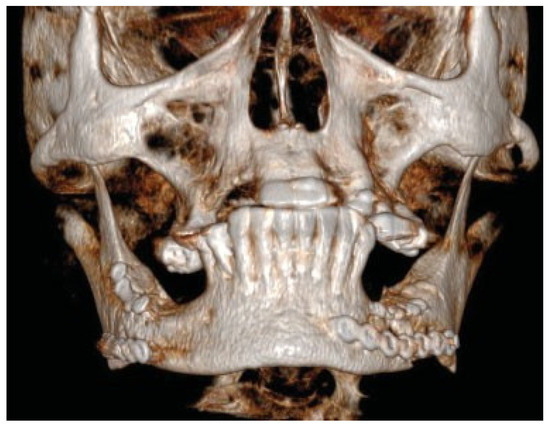

Immediate postoperative situation captured with CBCT.

Figure 12.

Six months follow-up. Clinical and radiological healing is seen in the previous fracture areas in the region of the first molar on both sides of the mandible.

Figure 13.